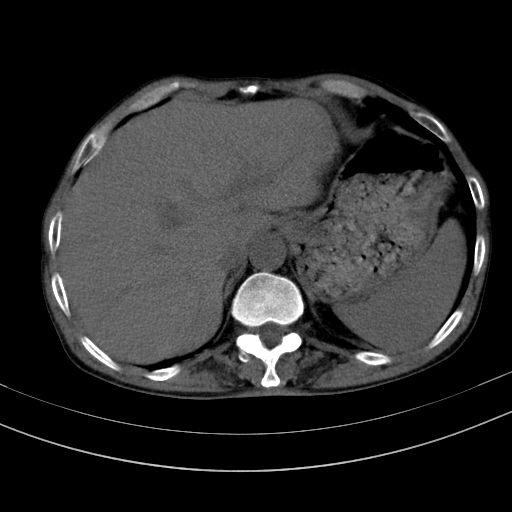

以下是引用dyqct在2010-1-9 17:56:00的发言:[br]考虑:1.双肾囊肿,左肾积水结石、旋转不良。[br] 2.右侧腹直肌血肿或纤维瘤。[br]肠道准备不好。做个增强。